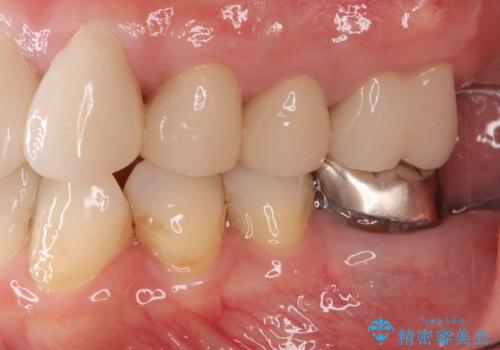

セラミッククラウンの治療は、天然の歯のような審美性を回復できることも大切ですが、精度が高くきっちりと歯ブラシを行いやすい状態を整えることで虫歯や歯周病の再発リスクを下げることも非常に大切です。